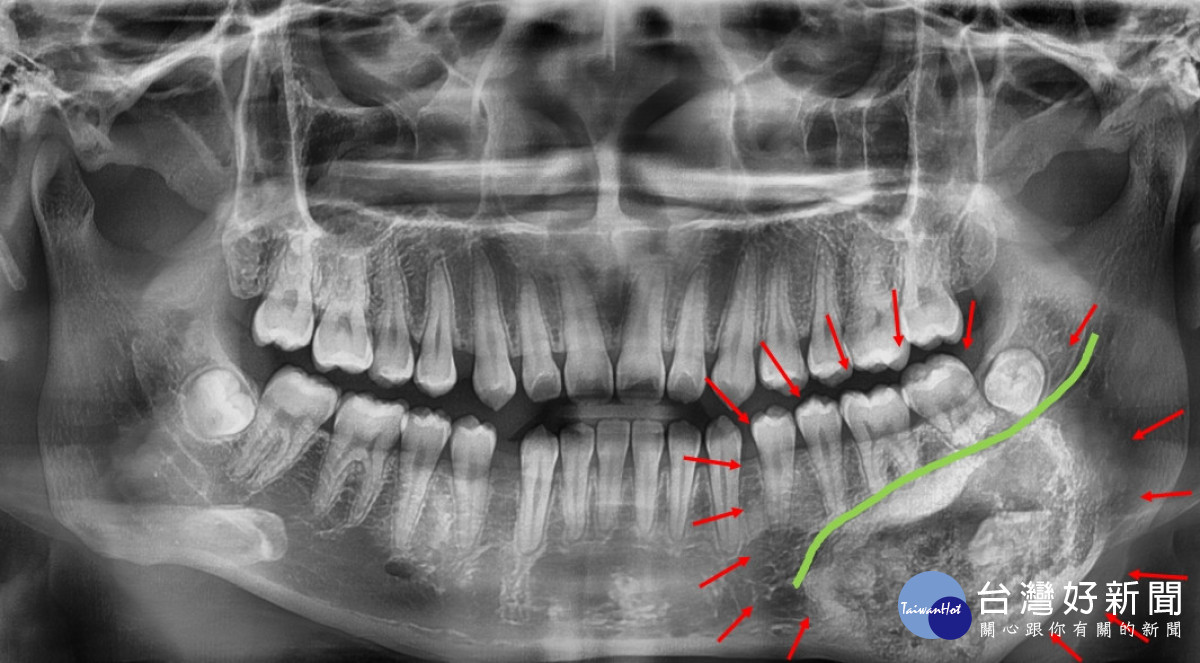

由於腫瘤邊界常與正常骨質交錯,若切除不夠精準,可能傷及下顎齒槽神經或導致顎骨變形。為提高手術安全與精準度,醫療團隊術前運用3D列印技術製作顎骨立體模型,模擬腫瘤切除範圍與重建角度,並以3D列印導引版輔助辨識神經走向與腫瘤邊界,規劃理想手術路徑。最終在完整切除腫瘤的同時,成功保留下顎齒槽神經,維持下唇感覺與口腔功能。

3D列印打造精準顎骨重建,秀傳醫療團隊助少女找回笑容。圖/記者鄧富珍翻攝